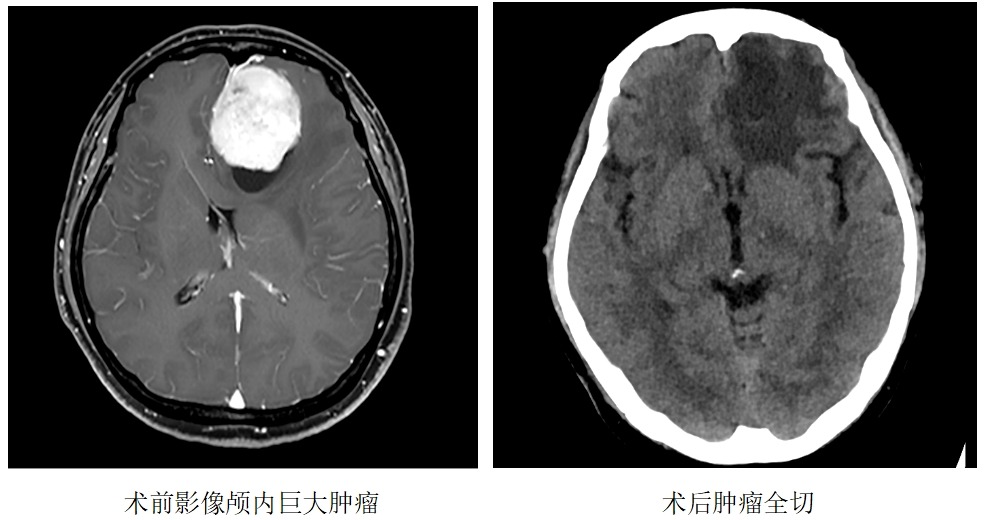

【医讯速览•新闻】第70期:我院神经外科成功完成了一例“颅内巨大肿瘤切除术”